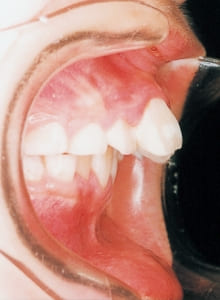

3 Initial Visit 2-11-’88

4 Initial Visit 2-11-’88

The Class II condition is pronounced, with a significant overjet of 12.5 mm(3). Although the teeth size are large, crowding is relatively mild. The maxillofacial structure has good depth and a robust bone framework(5). The mandible itself is solid , robust gonial angle, but there is significant anterior-posterior displacement relative to the maxilla(ANB 10.0°). While there is no confirmed history of thumb-sucking or similar habits, the lower lip is already pushing up against the maxillary incisors. The cause of this condition is unknown.